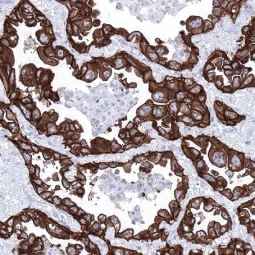

With this in mind, GeneTex is proud to introduce its HistoMAX product line that consists of antibodies specifically vetted for IHC. All of these reagents were extensively evaluated for IHC utilizing formalin-fixed normal and cancer tissue microarrays to guarantee specificity and best-in-class performance. Only antibodies that have passed these stringent performance criteria for IHC will be added to the HistoMAX portfolio.![]()